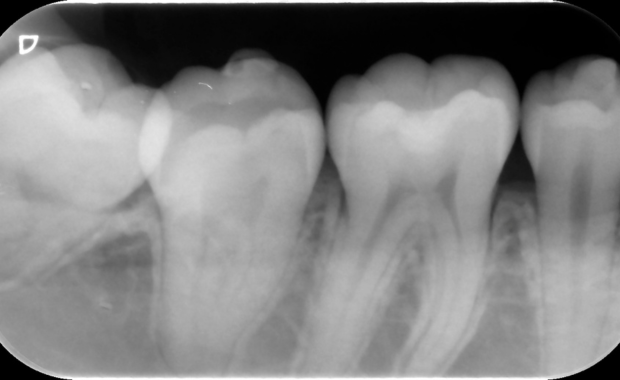

デンタルレントゲン

1〜3本の歯を詳細に映し出すための「精密検査用レントゲン」です。フィルムやセンサーを口の中に入れて撮影するため、細部の変化もはっきり映ります。虫歯の進行度、歯根の状態、詰め物・被せ物の適合性などを精査するために、必要な場合に撮影します。